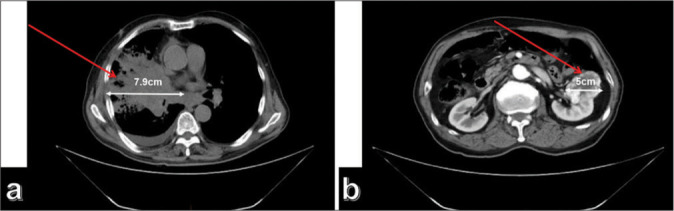

Few reports exist on dual primary lung and kidney tumors. Lung adenocarcinoma and renal clear-cell carcinoma are usually distinguished based on histological morphology and characteristic immunohistochemistry. This study describes a patient with concurrent lung adenocarcinoma and clear cell renal cell carcinoma, notable for their shared expression of both carbonic anhydrase IX (CA9) and cluster of differentiation 10 (CD10) markers, a phenomenon that has remained unreported in existing literature. We made a correct diagnosis based on histological morphology and immunohistochemical results, discussed the significance of CA9 and CD10 expression in lung adenocarcinoma, and provided insights for differential diagnosis, intending to offer pathologists relevant insights for diagnosing multiple primary malignant neoplasms.